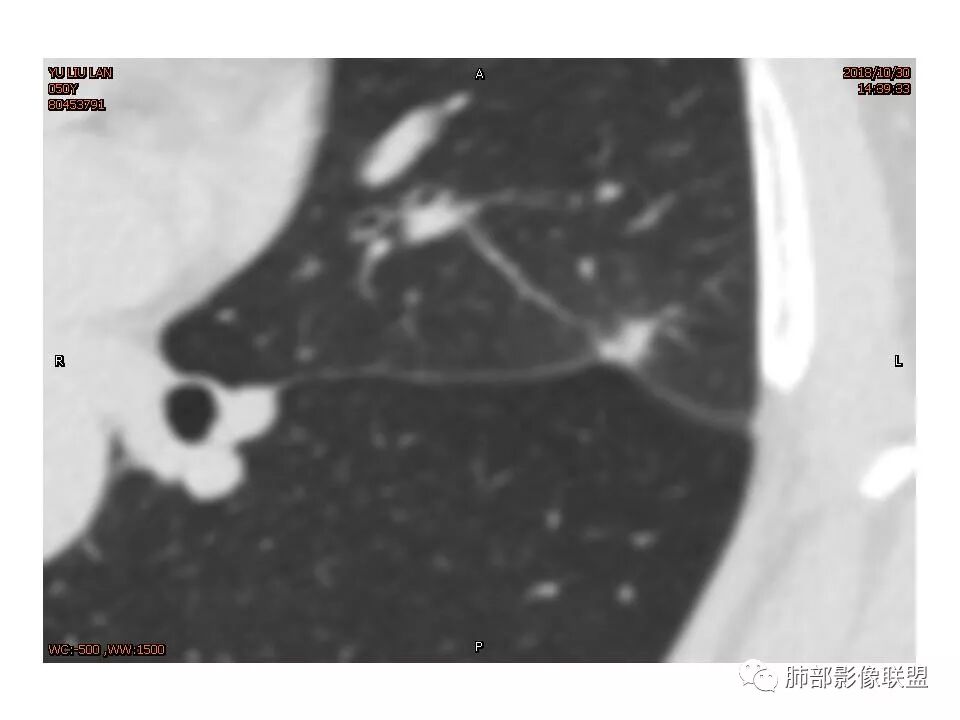

定位左舌,结节,有晕,晕中软毛刺,长毛刺与胸膜牵拉,收缩明显,部分呈方形,明显强化及延迟强化,有支气管近端进入远端阻塞,部分呈鬼脸

鉴别:腺癌 牵拉斜裂,有动静脉相连,

结节样病灶,u型征,病灶内可见细支气管管,增强可见血管进入,略增粗,病灶周围有晕,有软毛刺,局部叶间胸膜有牵拉,考虑良性炎性病灶,抗炎后复查。

尽管有收缩性改变,但是部分层面可见病灶有膨胀性表现,增强后病灶内可见血管影,局部血管凹凸不平,再加上病灶的分叶,胸膜凹陷征象等等,是不能排除恶性病变,写报告时,仍然需要把恶性病变靠前,腺癌第一考虑,其次炎性肌纤维母,再次再考虑炎性病变。

细小毛刺,梳状平行,周围边缘模糊晕,血管未收侵犯,支气管未见牵拉扩张,多条淋巴道与胸膜相联,倾向于炎性病变

长毛刺比较软。旁边是卫星灶吗?

1.胸膜下略不规则实性密度结节影,孤立,缺乏典型深分叶,可见淡薄边界模糊磨玻璃晕,可见相对细长软毛刺。

2.如南边老师分析,病灶缺乏边缘膨隆优势,甚至部分平直内收。

3.病灶收缩力不强,整体强化程度不显著。